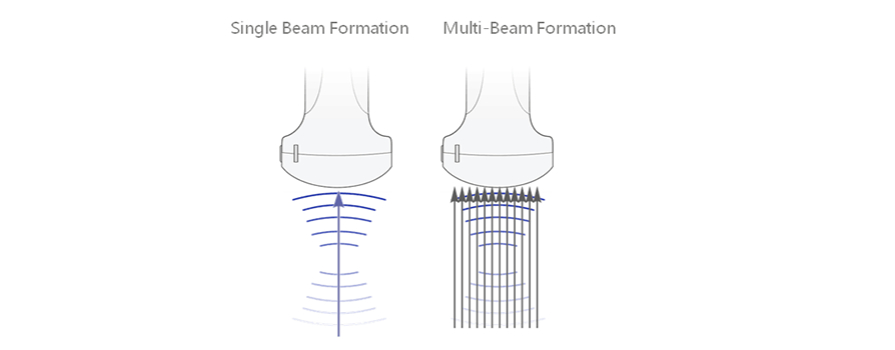

iBeam?

?? ?? ?? ??? ???? ?? ??? ??? ? ?? ?? ???? ???? ???? ??????